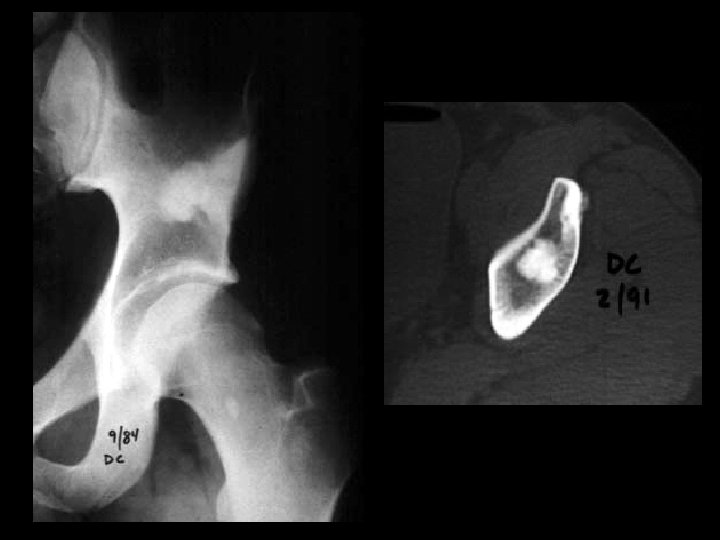

Osteoma • Findings: – Well-defined lesion of compact bone involving the left ileum – No change over many years • ddx: – Sclerotic metastasis